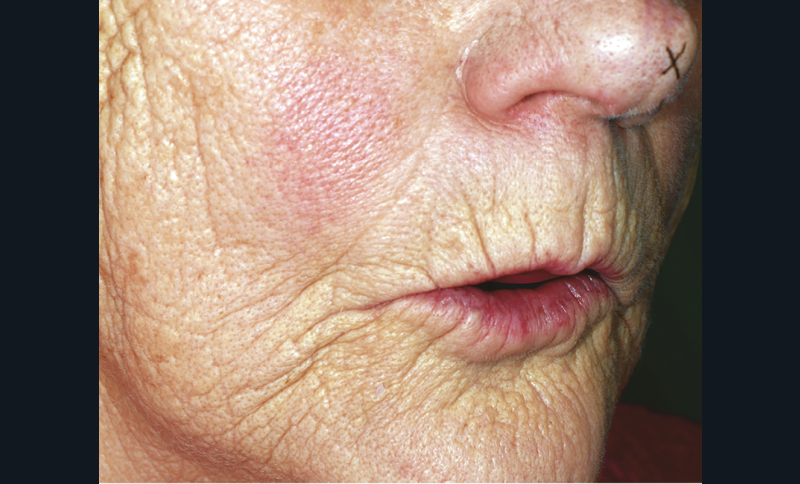

La sous-évaluation, quant à elle, engendre un impact esthétique avec un affaissement de l’étage inférieur de la face. Le patient paraît vieilli, avec un approfondissement des rides et sillons du visage, le menton avance (fig. 2). La déglutition peut être inconfortable, avec une interposition labiale fréquente. Toutefois une légère sous-évaluation engendre peu de conséquences ; le patient aura même tendance à se sentir plus confortable avec ses prothèses.